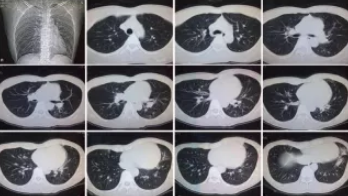

CT檢查

CT檢查原理是X光分層穿過人體,這就像把面包切成薄片,每一片都可以攤開看。當遇到外傷懷疑傷到骨頭,可以選擇CT觀察隱匿損傷或軟組織損傷。

CT適用于頭部、胸部、腹部、盆腔、脊柱、四肢、骨骼等處,由于它的特殊診斷價值,已經廣泛應用于臨床,特別是在腫瘤的診斷上更是具有很高的應用價值。但由于CT設備較為昂貴,檢查費用也會偏高,對于某些部位的檢查和診斷價值,尤其是定性診斷,還有一定限度,所以在臨床上并沒有將CT檢查視為常規診斷手段。此外,CT診斷輻射量大于DR,所以懷孕或備孕期女性不宜進行CT檢查。